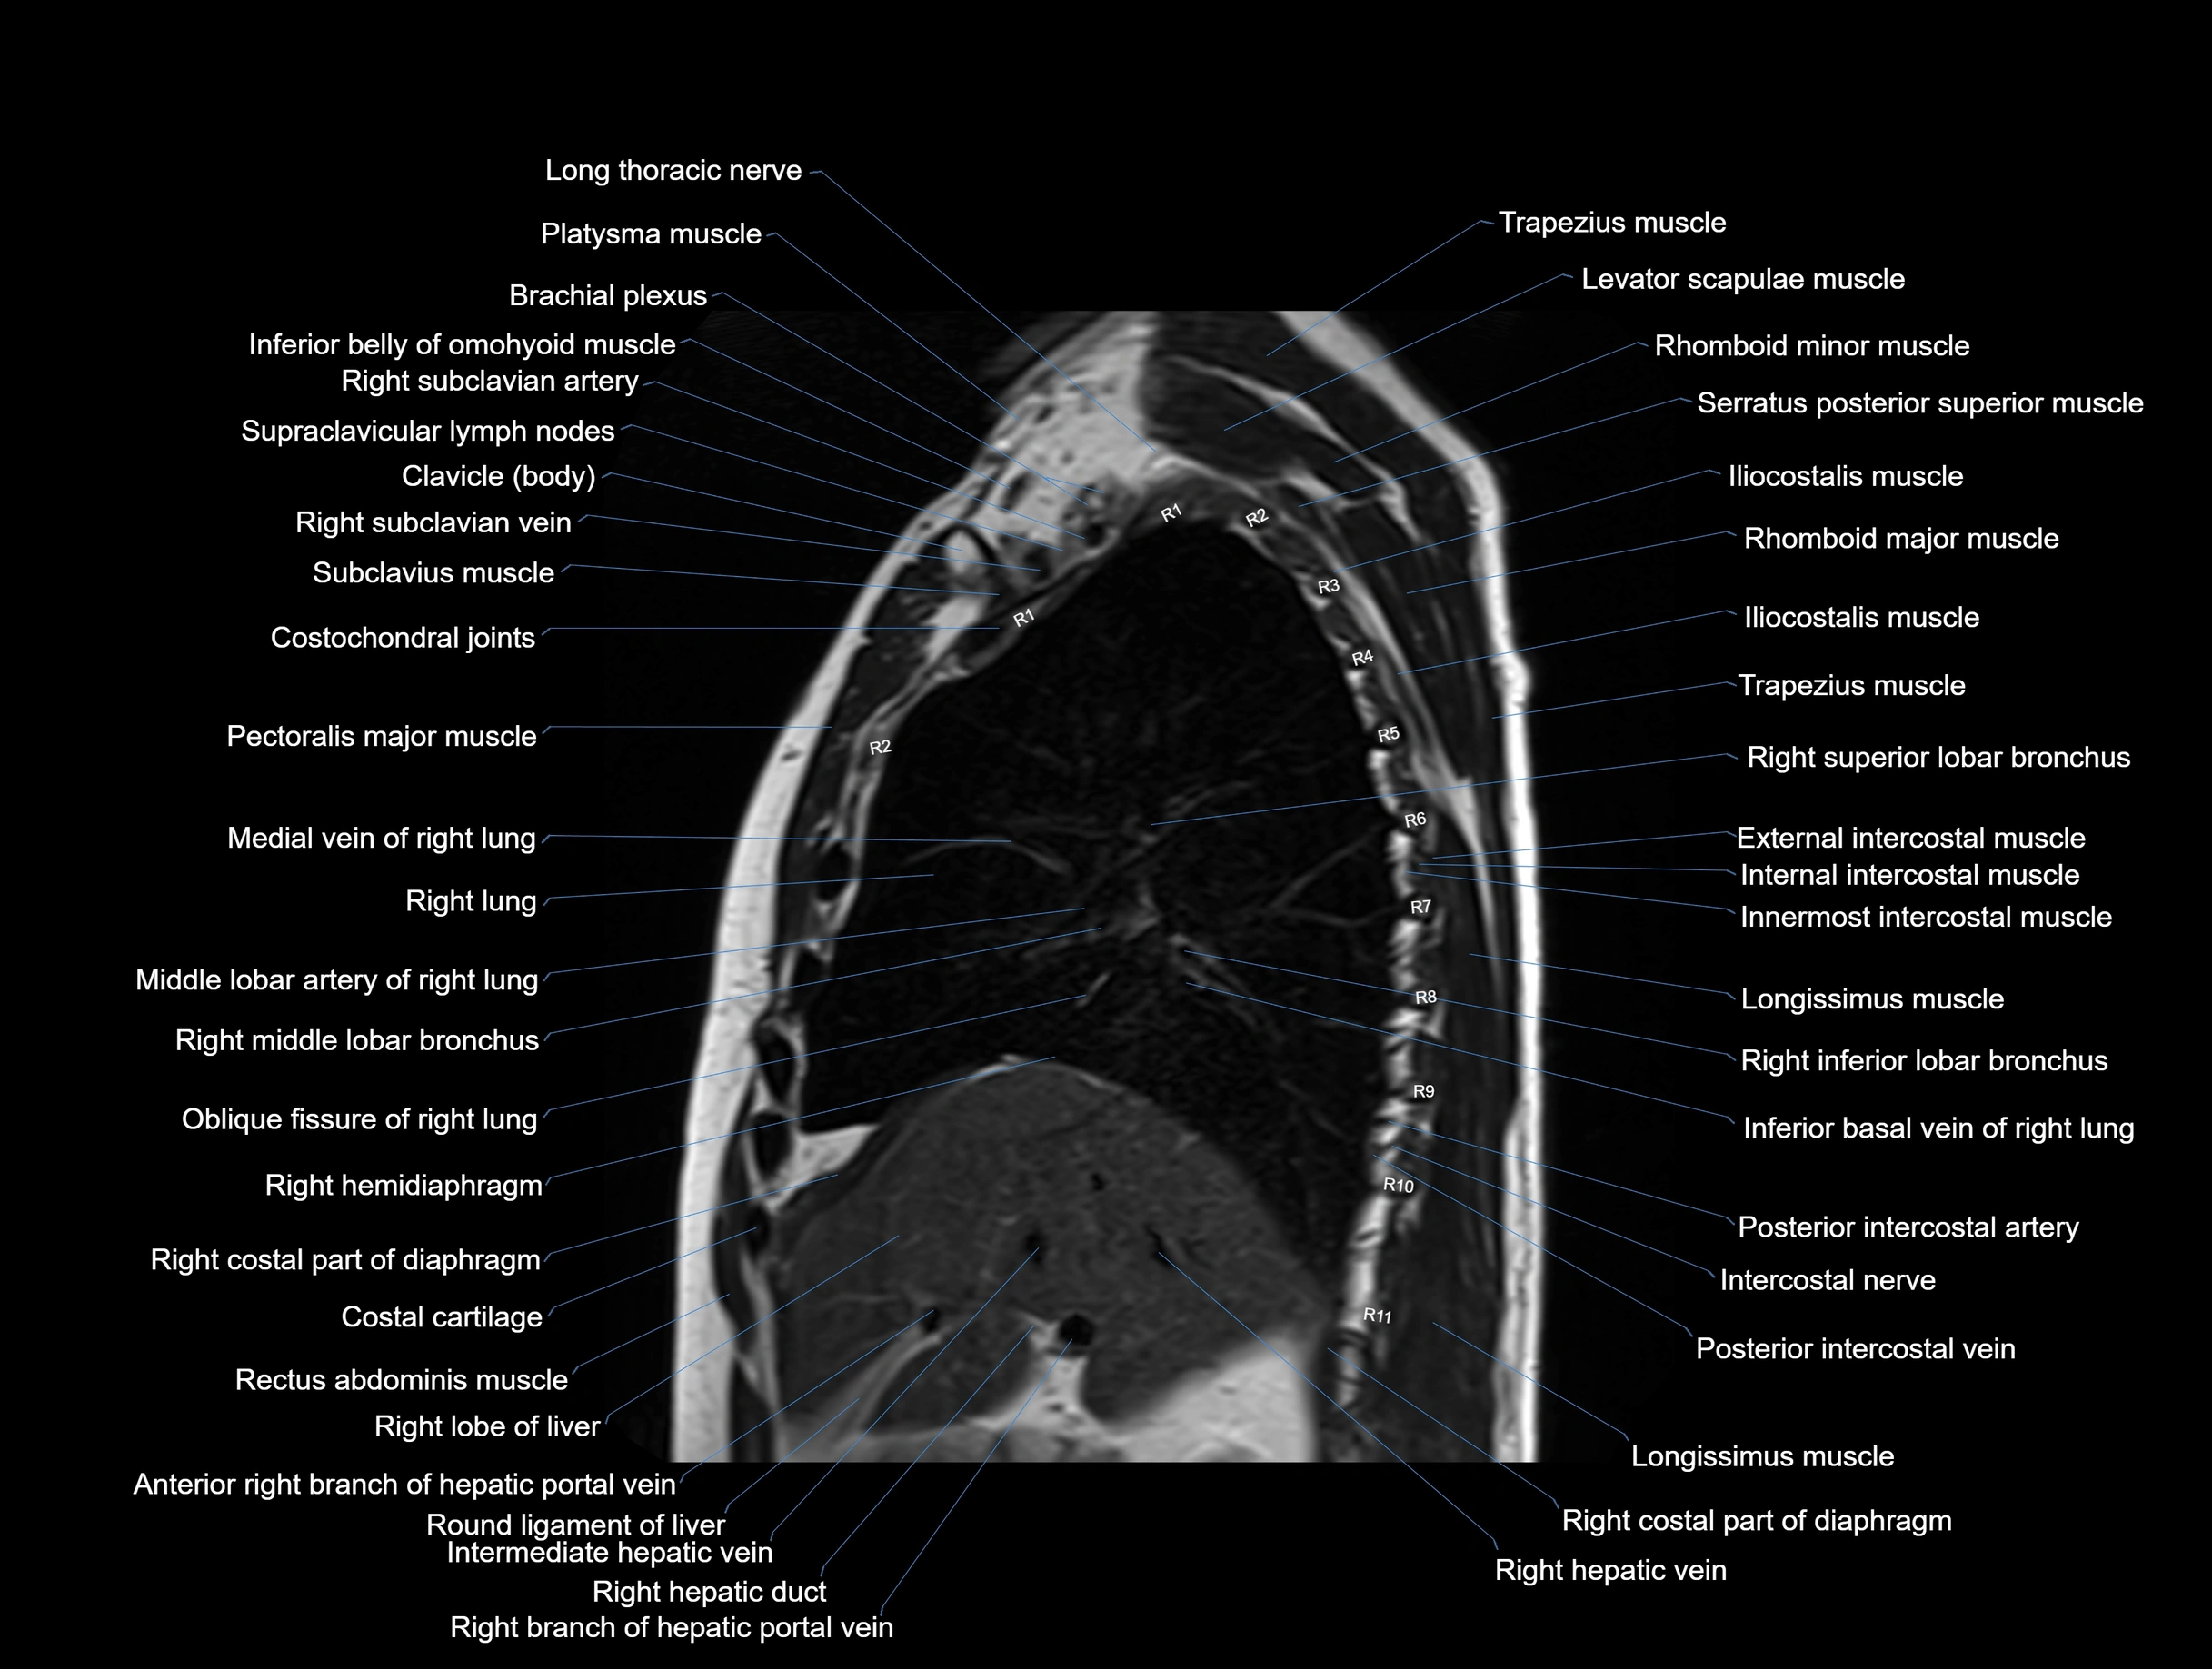

MRI images